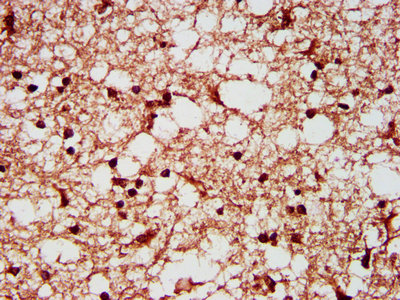

IHC image of CSB-PA021125LA01HU diluted at 1:200 and staining in paraffin-embedded human glioma performed on a Leica BondTM system. After dewaxing and hydration, antigen retrieval was mediated by high pressure in a citrate buffer (pH 6.0). Section was blocked with 10% normal goat serum 30min at RT. Then primary antibody (1% BSA) was incubated at 4°C overnight. The primary is detected by a biotinylated secondary antibody and visualized using an HRP conjugated SP system.